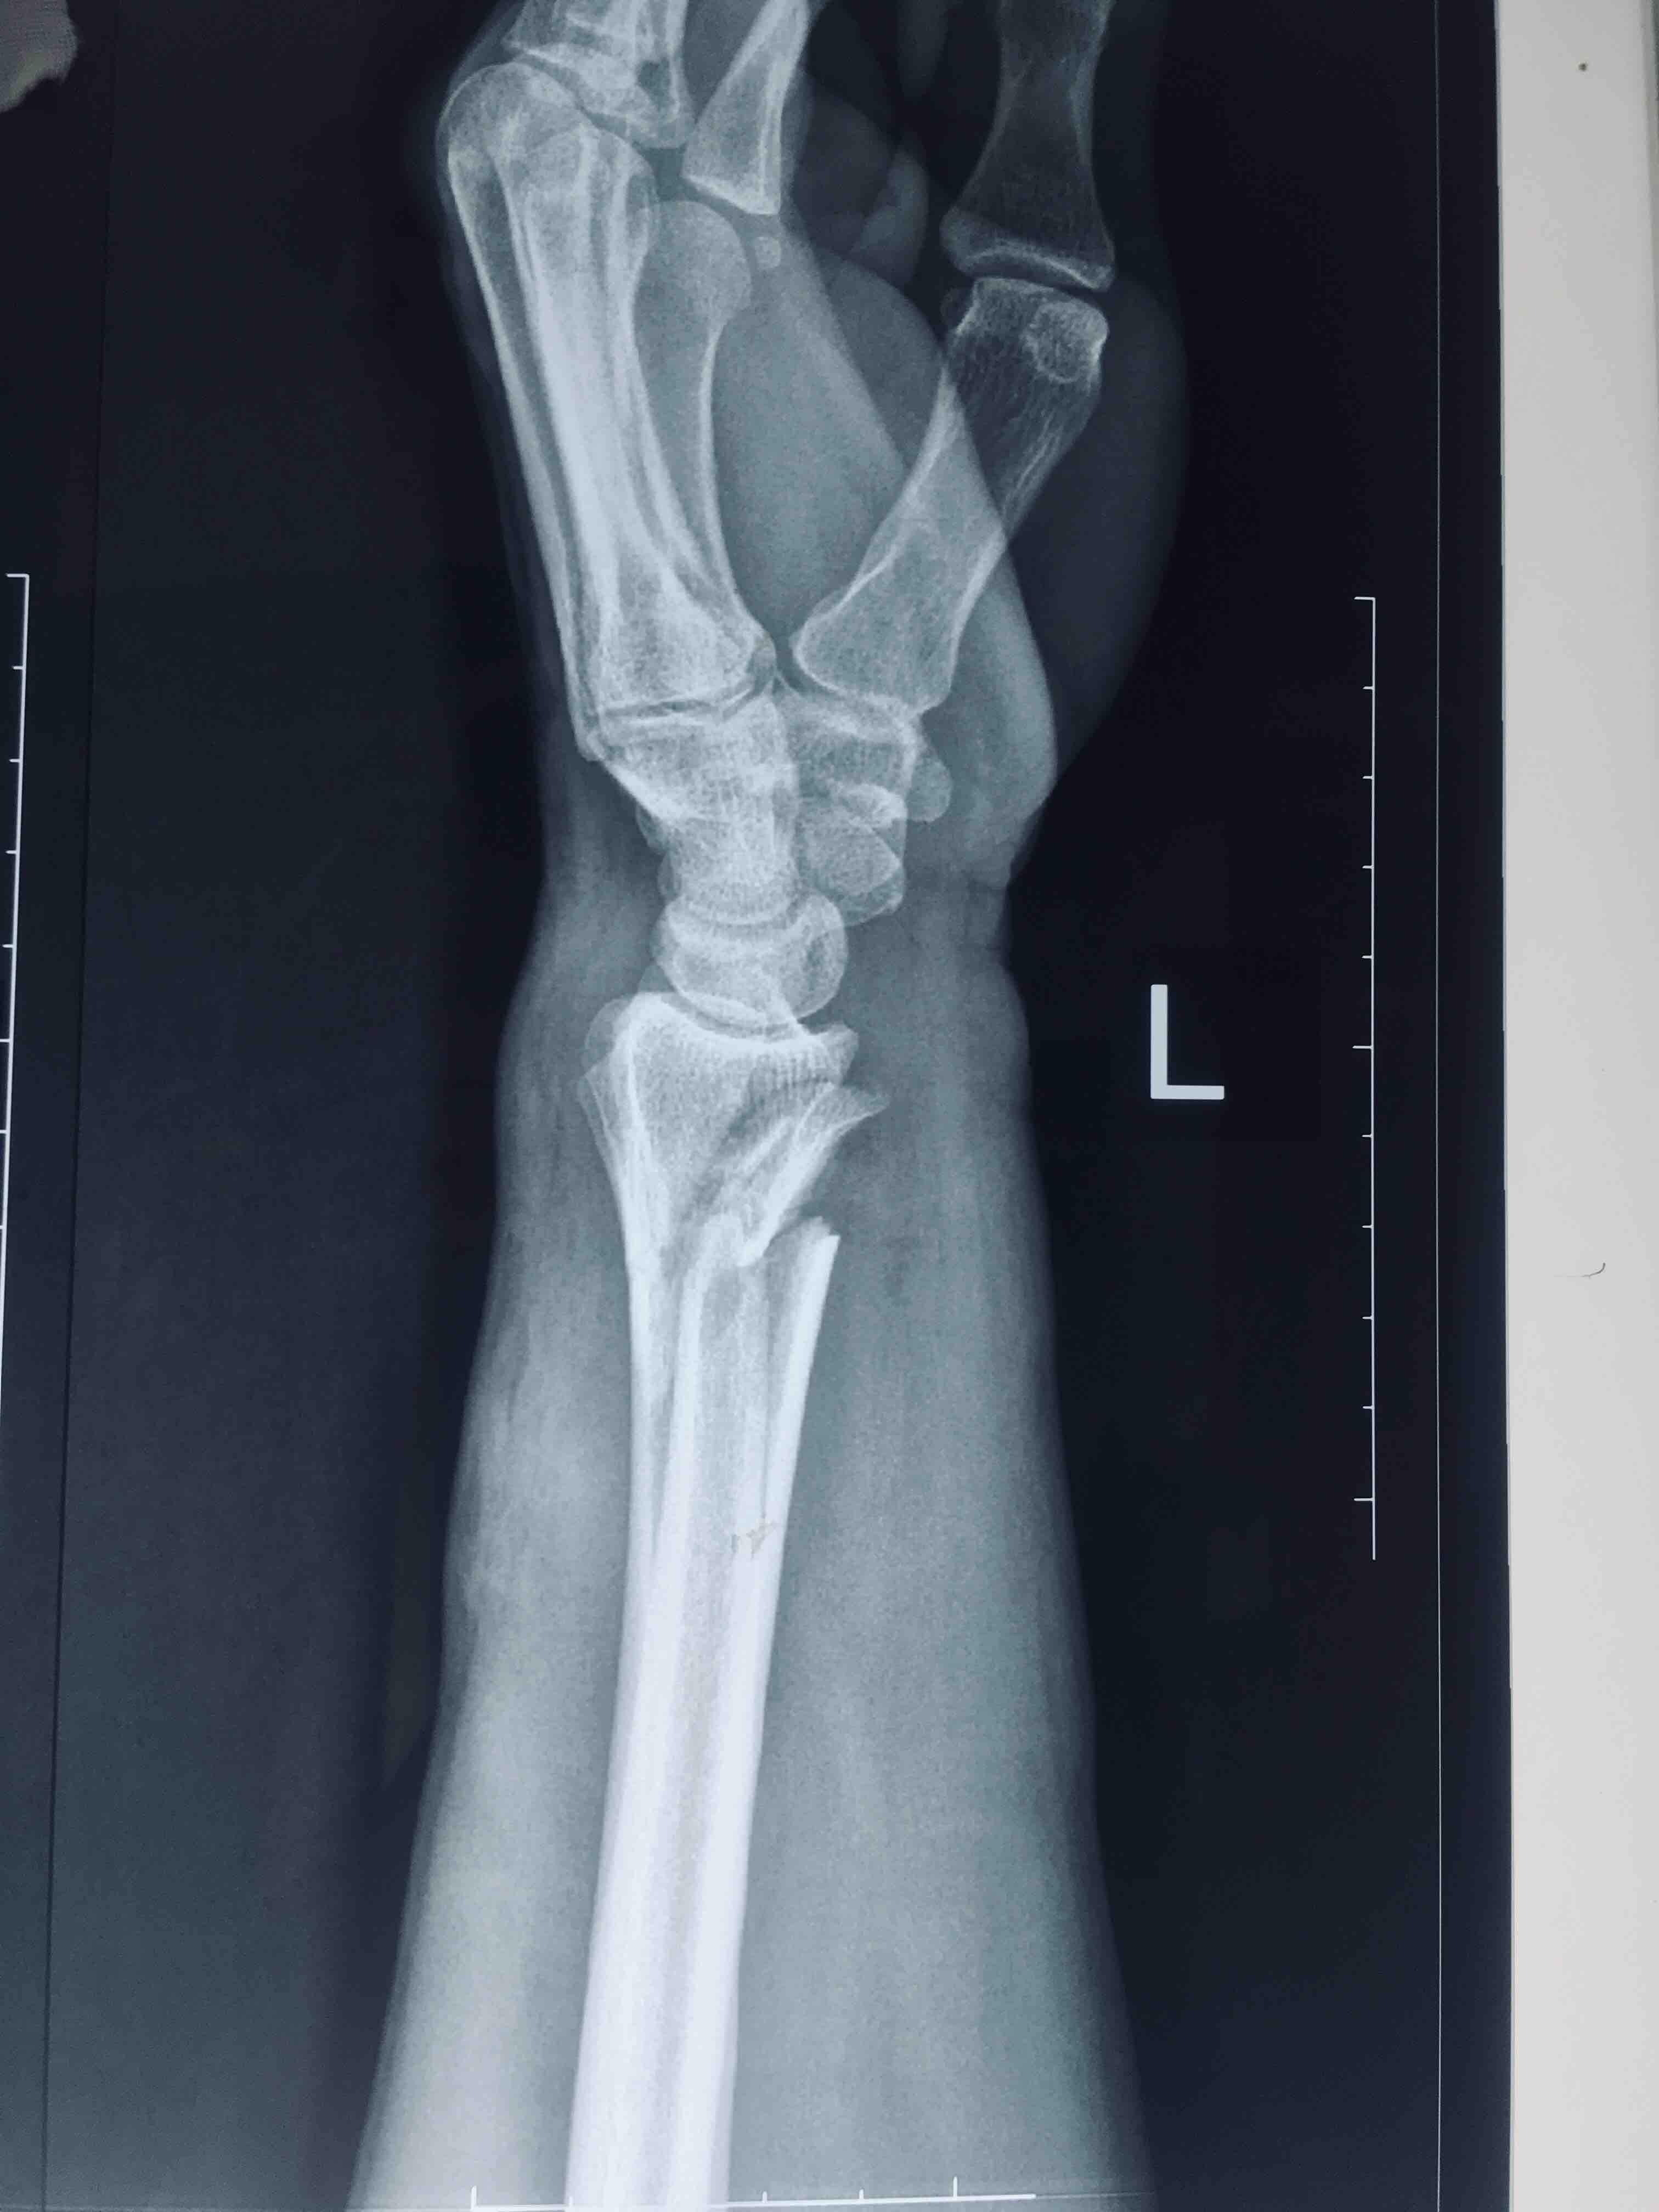

尺桡骨远端骨折合并拇长屈肌腱断裂,正中神经损伤

摔伤后左腕部肿胀疼痛1小时入院。既往身体健康,无特殊不良癖好。

生命体征平稳,心肺复未见异常。左腕部肿胀明显,畸形,皮色发红,皮温高,压痛及纵向叩击痛阳性,拇指屈指受限,正中神经支配区各指麻木,末梢血运正常。